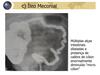

Ileo meconial

- o mecônio é formado durante a gestação por todos os elementos do líquido amniótico ingerido pelo feto, céls epiteliais da mucosa intestinal - chamamos de doença meconial a síndrome da rolha meconial e o íleo meconial - costuma ter evolução benigna - pode ser um sinal de doença de hirschsprung ou fibrose cística - 10-15% de crianças com fibrose cística vao apresentar íleo meconial. Nessas crianças, pela deficiência exócrina, o mecônio tem menos água, baixo níveis de sacarase, lactase e enzimas pancreáticas e nível aumentado de albumina - normalmente a obstrução ocorre no nível da valvula íleo-cecal - rx: vidro moído (mecônio espesso), bolha de sabão (bolhas que se misturam ao mecônio) - enema contraste: microcolon em desuso - tto: enema com contraste hidrossolúvel guiado por fluoroscopia ou enema com N-acetil-cisteína. A irrigação dissolve o mecônio espesso e permite sua passagem. Nos casos refratários, LE + enterotomia com irrigação + ileostomia (irrigação no pós op) * íleo meconial complicado são aqueles que o paciente apresenta perfuração, volvo, gangrena ou atresia intestinal